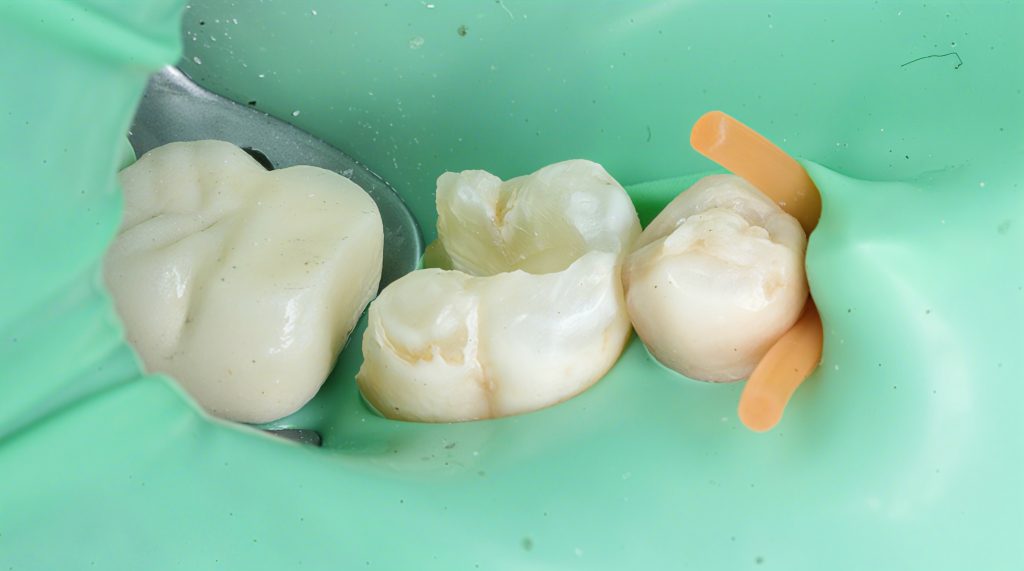

The tooth presented with a large carious lesion extending sub-crestally on the distal, compromising the marginal integrity and leaving no clean, dry, enamel-based margin for adhesive bonding. A single-visit root canal treatment was completed, followed by a staged Deep Margin Elevation (DME) to relocate the margin supragingivally. The case was finished with full cuspal coverage using a biomimetic composite onlay under rubber dam isolation.

5. Cuspal Coverage / Composite Onlay

- Enamel cleaned and selectively etched.

- Universal adhesive applied following manufacturer protocol.

- Cuspal reconstruction done anatomically.

- Occlusal anatomy built cusp-by-cusp, guided by natural morphology.